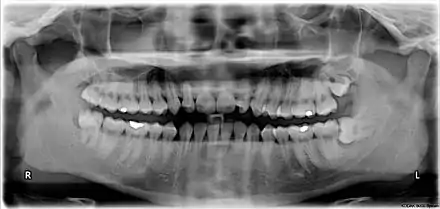

Risk factors of inferior alveolar nerve damage

Temporary and permanent inferior alveolar nerve (IAN) damage is a known complication of the surgical removal of impacted lower third molars, happening in 1 in 85 patients and 1 in 300 extractions, respectively. Studies have shown that certain risk factors may increase the likelihood of IAN damage. Proximity of the impacted third molar root to the mandibular canal, which can be seen in radiographs, has been shown to be a high-risk factor for IAN damage. Alongside this, the depth of impaction of the tooth, surgical technique and surgeons experience are all contributing risk factors for IAN damage during this procedure. Careful case-by-case consideration is crucial to avoid this risk.[39]